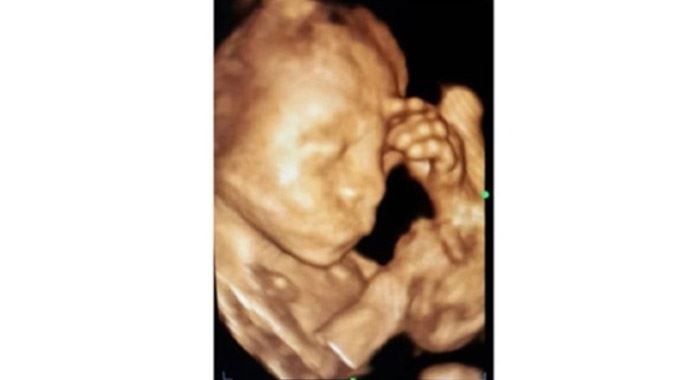

Anne karnındaki bebeğin şaşırtan fotoğrafı

Konya'da 23 haftalık bebeğinin anne karnında elini başına koyarak düşünen hali ultrason ile kaydedildi.

Konya'nın Ereğli ilçesinde bir anne adayının kontrol edilen 23 haftalık kız bebeği 4 boyutlu ultrason cihazında elini başına koyarak düşünürken görüldü. Gördüğü manzara karşısında şaşıran Kadın Doğum Uzmanı Op. Dr. Kadriye Turgut bu anı ölümsüzleştirerek fotoğraf olarak kaydetti.Anne karnında bebeğin annenin yaşadığı mutluluğu, sevinci, üzüntüyü hissediyor olarak bilinmesi, kaydedilen bu fotoğraf ile 'acaba bebek annesinden mi etkileniyor' düşüncesini akıllara getirdi.